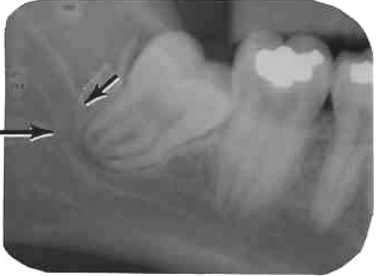

33. What is showing by arrow?

34. What is showing by arrow?

35. What is showing by arrow?

36. What is showing by arrow?

37. What is the anatomical structure indicated by arrow in this radiograph?